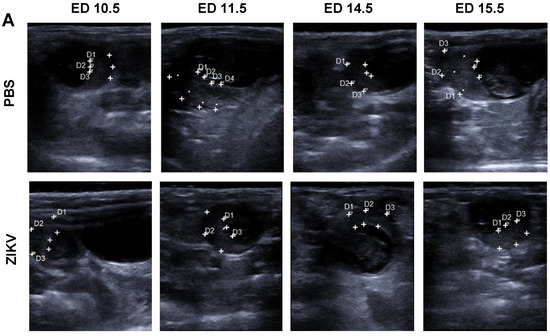

The placenta is considered as an important target organ for ZIKV infection resulting in direct transmission to the fetus [14,15]. Our USI data from pregnant mice demonstrated that the placenta can be detected as a clearly visible structure. To characterize the influence of ZIKV infection on the placental functionality in more detail, we comparatively monitored shape, thickness, and texture of the placenta in USI (Figure 3A). On ED 11.5, we observed no big differences in the placental thickness between ZIKV-infected and control mice with a mean thickness of 1.8 mm and 2.0 mm, respectively. Direct comparison in USI also indicated no obvious differences in the organ texture and density. However, on ED 14.5, placental thickness in ZIKV-infected mice was significantly lower than in the mock-infected control mice (Figure 3A,B). The mean thicknesses for the two groups were 1.96 mm and 2.82 mm respectively (Figure 3B). In addition, USI revealed a modified appearance of the placental texture. Placentas from ZIKV-infected mice were brighter compared to the placentas of PBS controls indicating a higher echogenicity and echotexture. In contrast, the PBS infected placentas remained visible as a crescent shape with light colored staining (Figure 3A). This data was confirmed by uteroplacental pathology including histopathological analysis at the end of the experiment. Interestingly, the absolute placental weight was significantly lower in ZIKV-infected mice compared to controls (Figure 3C). The mean placental weight in the PBS control group was 0.125 g whereas placentas from ZIKV-infected mice had a mean weight of 0.05 g only. Moreover, the histopathological examination also revealed features of ZIKV infection in agreement with the differences in thickness and echogenicity determined by USI on ED 11.5.

Figure 3.

ZIKV induced changes in the placenta; (A) Measurement of placenta thickness by ultrasound imaging. Representative images from ED 10.5, 11.5, 14.5, and 15.5 are depicted for PBS control mice and ZIKV-infected mice; (B) Comparative evaluation of placental weights on ED 16.5 in sacrificed mice (n = 8–10 mice per group; differences between individual groups were analyzed by Mann–Whitney test. Error bars indicate the interquartile range (IQR) from the median. Asterisks represent statistically significant differences between two groups: **** p < 0.0001; (C) ZIKV challenge of pregnant mice results in highly productive ZIKV infection of placental tissues, virus titers in placentas after ZIKV infection. At the end of the experiments (ED 16.5) placentas were removed and homogenized, and the amount of virus was determined by plaque assays (n = 31–39 placentas per group); data are representative of at least two independent experiments; differences between individual groups were analyzed by Mann–Whitney test. Error bars indicate the interquartile range (IQR) from the median. Asterisks represent statistically significant differences between two groups: **** p < 0.0001; (D) placental diameter determined by ultrasound-based measurements comparing ED 11.5 and ED 14.5 (n = 31–39 placentas per group); data are representative of at least two independent experiments; differences between individual groups were analyzed by Mann–Whitney test. Error bars indicate the interquartile range (IQR) from the median. Asterisks represent statistically significant differences between two groups: **** p < 0.0001; (E–G) (De) decidua, (BZ) basal zone, (LZ) labyrinth zone, (CP) chorionic plate, and (YS) yolk sac. Histological analysis of placental tissues following ZIKV infection; (E) Placentas were removed, and sections of the organs were routinely stained with hematoxylin and eosin (HE) Bar = 300 µm; (F) Sections of tissues were treated with von Kossa staining to identify tissue calcification Bar = 100 µm; black asterisks indicate accumulations of dystrophic mineralization in the basal LZ of ZIKV-infected mice; (G) Placenta, ED 16.5, immunohistochemical staining with αZIKV. Variable, prominent intracytoplasmic antigen expression in the chorionic epithelium (black arrow), in spongiotrophoblasts and glycotrophoblasts (inset) of the ZIKV-infected group, whereas all placentas of the control group including their chorionic epithelium (black arrow) were immunonegative. Bar = 100 µm.

Finally, when monitoring virus loads, we found large amounts of virus in the placentas of ZIKV-infected mice corroborating their importance as target organ during in vivo infection (Figure 3D). Placentas of ZIKV-infected mice showed extensive ZIKV-specific staining, primarily in areas of the labyrinth zones severely affected by inflammation (Figure 3E). Several trophoblasts lines, like glycogen trophoblasts, spongiotrophoblasts, and to a lesser extent cytotrophoblasts and syncytiotrophoblasts showed antigen expression in a variable amount. Upon H&E staining, we detected large areas of densely packed inflammatory cells, mainly comprising lymphocytes and scattered macrophage-like cells as well as granulocytes in placentas from ZIKV-infected dams. Especially in the labyrinth zone, there seemed to be irregular shaped fetal capillaries in decreased numbers. Interestingly, these inflammatory processes seemed to be mainly associated in the labyrinth layer resulting in an obvious thinning of the placenta compared to mock-infected control mice (Figure 3F). Since IHC confirmed a direct ZIKV infection of placental cells, we aimed to correlate the reduced echogenicity in USI with direct effects of ZIKV infection. Of note, we specifically detected the presence of placental calcifications by Kossa-specific staining in the tissues from ZIKV-infected mice (Figure 3G). Interestingly these calcifications were mainly seen in the labyrinth zones around smaller vessels and some were filled with erythrocytes. Calcifications were visible in the basal labyrinth zone near the chorionic epithelium of infected mice, whereas in the control group this was not visible.